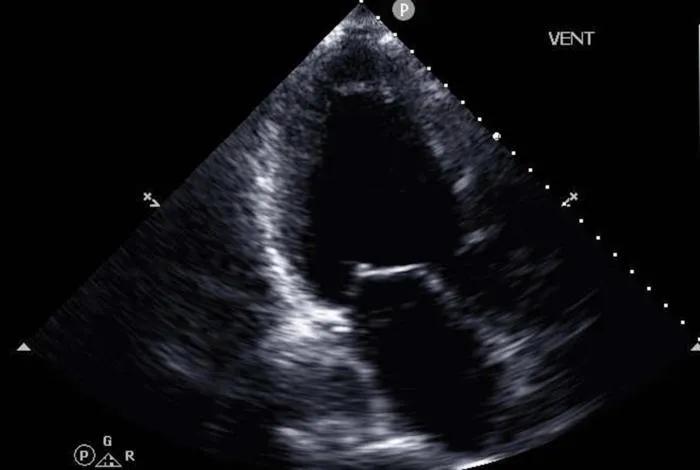

Researchers have developed an AI tool that accurately diagnoses advanced heart failure using cardiac ultrasound and patient health records.